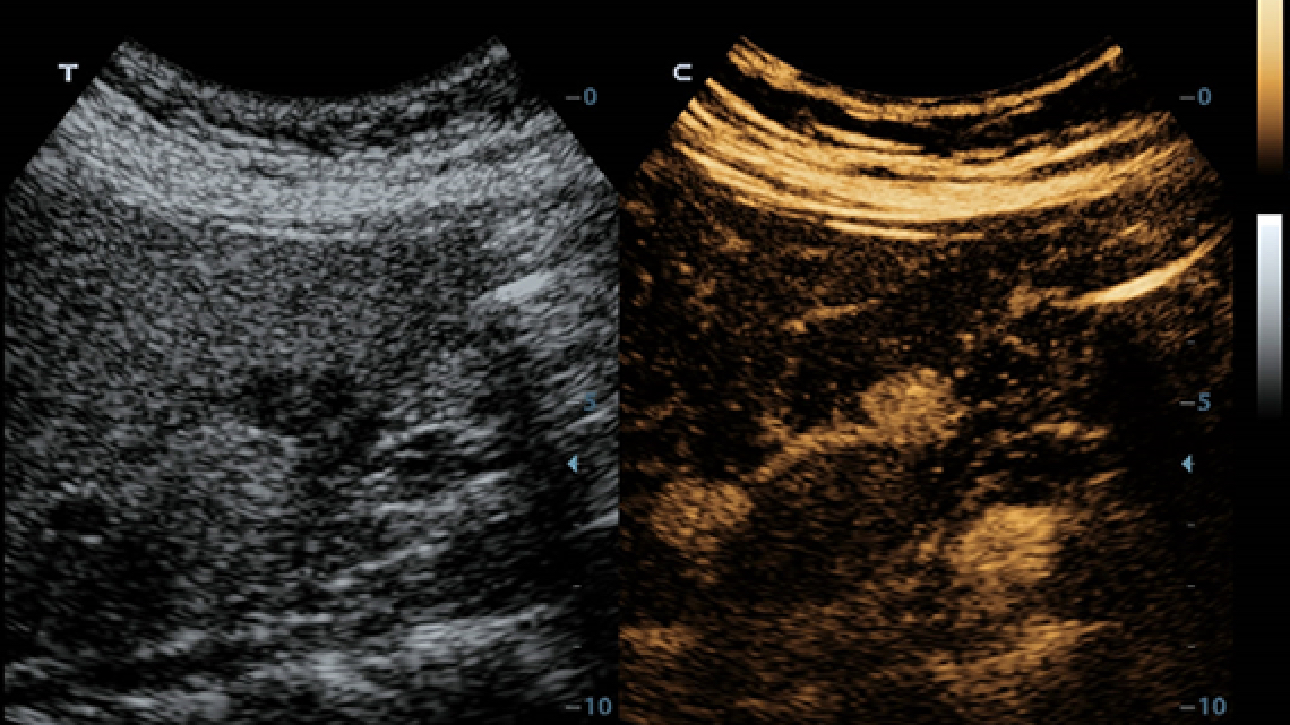

Klinische Bilder

Schallk?pfe